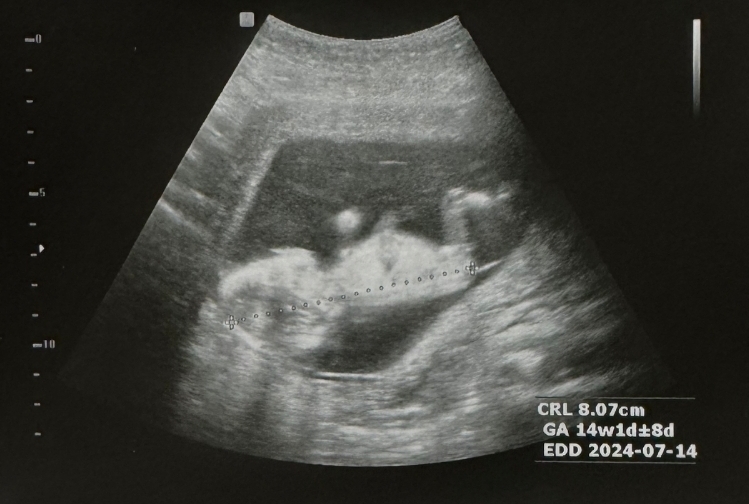

14주 고수분들 판독부탁드려요 제발용!

14주3일차입니다!! 고수분들이보시기엔 어때보이세요??? 고수분들 의견좀주세요!

흐리지만 딸같아염

살짝 아들같아요~😀

고수는 아니지만 딸같아요😆